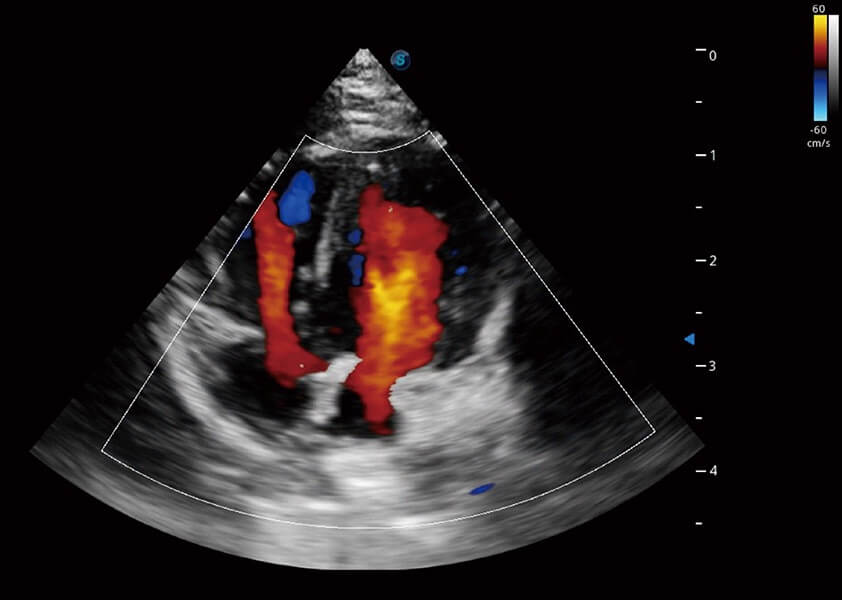

ProPet 60 作为一款高端台式动物超声设备,为动物医生的日常诊断提供了一系列贴合动物临床需求、解决临床实际问题的高级成像功能。凭借全系列高清探头,满足医生对腹部、心脏、生殖、浅表、肌骨等成像的所有需求,切实帮助您提升检查效率,提高诊断信心。

动物是人类最亲密的朋友和最值得信赖的伙伴。银河集团官网也一直致力于探索动物专用的超声影像解决方案。 全新推出的ProPet系列,是银河集团官网在动物超声影像智能化、专业化、精准化的一次跨越式革新。动物不能用言语来表述自己的不适,通过超声影像,ProPet系列搭建了动物医生与不同物种沟通的“桥梁”,为动物医生注入了“治愈之力”。